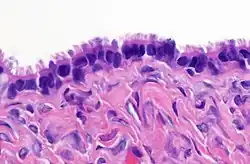

| High magnification micrograph of a Brenner tumor, a type of surface epithelial-stromal tumor. H&E stain. | |

Brenner tumor

Brenner tumors are uncommon surface-epithelial stromal cell tumors in which the epithelial cell (which defines these tumors) is a transitional cell. These are similar in appearance to bladder epithelia. The tumors may be very small to very large, and may be solid or cystic. Histologically, the tumor consists of nests of the aforementioned transitional cells within surrounding tissue that resembles normal ovary. Brenner tumors may be benign or malignant, depending on whether the tumor cells invade the surrounding tissue.